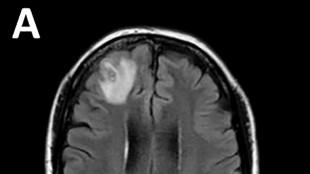

Un ver rond, qui parasite généralement les serpents, a été découvert pour la première fois sur un être humain, extrait "vivant et se tortillant" du cerveau d'une Australienne lors d'une intervention chirurgicale, ont annoncé mardi des médecins australiens.